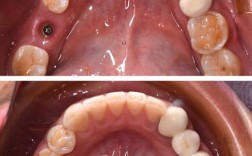

(图片来源网络,侵删)- 这是使用树脂充填器前最关键的步骤! 湿气是树脂充填失败的常见原因。

(图片来源网络,侵删)- 材料选择: 根据修复部位选择合适的树脂(通用型、纳米树脂、混合树脂、流动树脂等)。